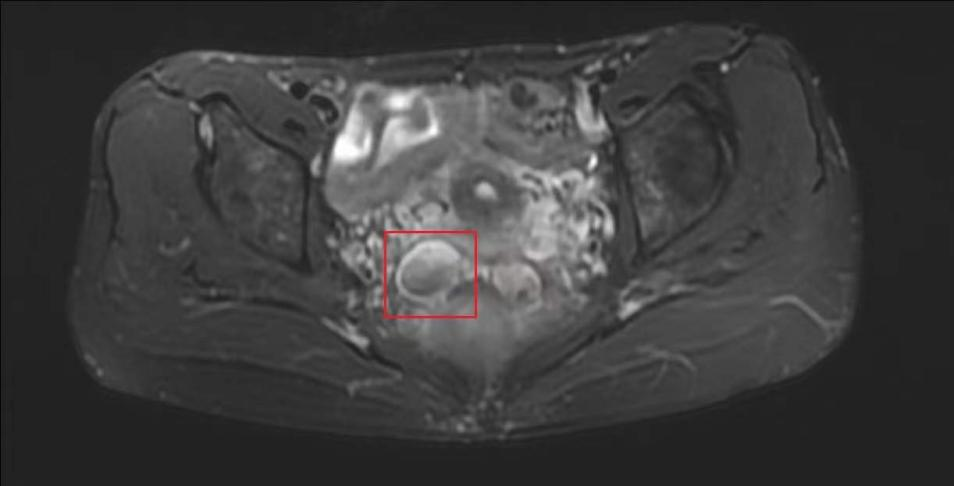

“每天大便7、8次,每次都非常痛。”王女士摇摇头说道,“每次量很少,小便也有困难,而且肛门坠胀感十分强烈。”王女士多次在其他医院胃肠外科治疗效果不佳,到南方医科大学中西医结合医院就医后接受结肠镜、超声肠镜等检查均未见异常,但在下腹部MR扫描时,发现“子宫直肠窝数个囊状异常信号,考虑巧克力囊肿”以及“左附件区囊性病变,考虑卵巢巧克力囊肿”。曾朝阳介绍,巧克力囊肿指的是陈旧性积血的囊肿,因为呈褐色,黏稠如糊状,似巧克力,故被称为“巧克力囊肿”。

子宫直肠窝囊状异常信号,考虑巧克力囊肿

子宫直肠窝囊状异常信号,考虑卵巢巧克力囊肿